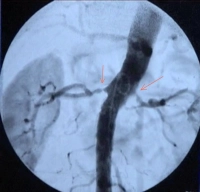

Gestão perioperatória - Angioplastia transluminal percutânea (PTA) e colocação de stent em estenose bilateral da artéria renal - Cirurgia vascular

• RAS unilateral ou bilateral de alto grau (>70%) com o objetivo de preservação de órgãos (veja a indicação no clipe de vídeo)